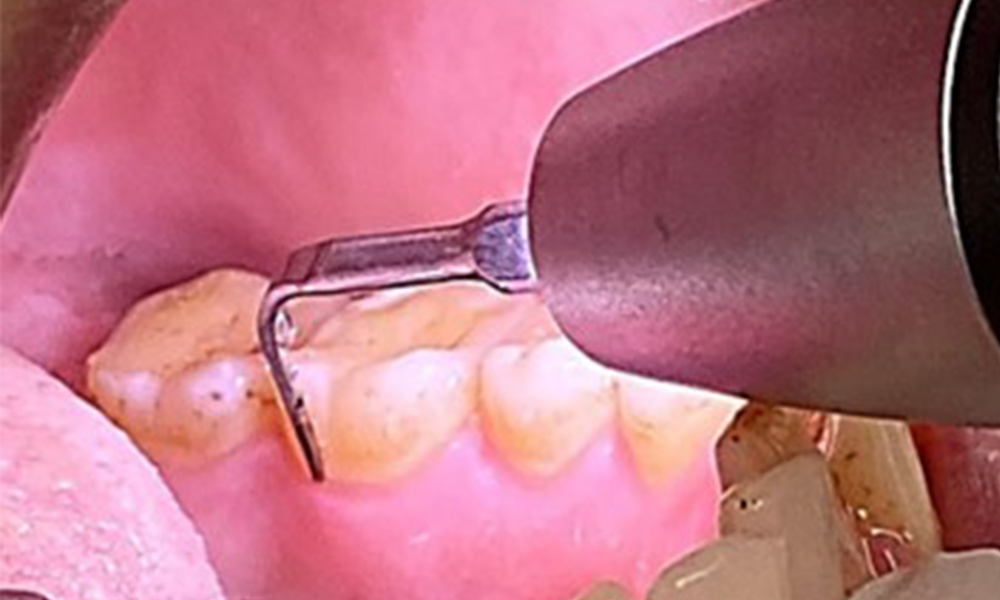

Due to the otherwise favourable general medical condition, the needs determined during the intraoral examination will be decisive for their treatment. It will be essential to periodically determine the probing depths. Gingival bleeding decreases in smokers, which is why the clinical diagnosis of periodontitis can only be made by probing (Fig. 7). Placing exclusive focus on the determination of bleeding indices may obscure existing periodontitis or gingivitis. (5)

Pocket probing (BOP) with depiction of tooth 36 lingual

Fig. 7 Pocket probing (BOP) with depiction of tooth 36 lingual, © Dr R. Krapf

The objective would be to control disease risk by removing supragingival and subgingival biofilm. The instruments can be selected based on patient needs. First, calculus and any concretions must be removed using ultrasonic and/or manual instruments (Fig. 10).

Use of a piezo-driven ultrasonic device in the lingual area near 36

Fig. 10 Use of a piezo-driven ultrasonic device in the lingual area near 36 (Proxeo Ultra, W&H, shown here), © Dr R. Krapf